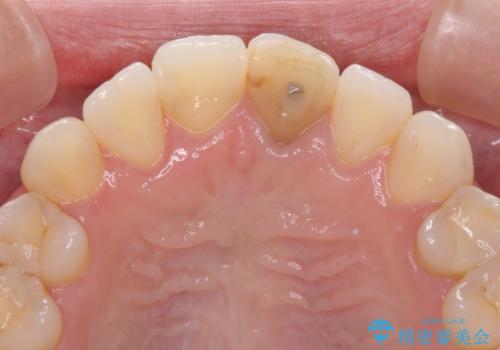

- 前歯のクロスバイトと神経を取り除いた後に変色してしまった前歯を気にして来院された患者様です。

ワイヤー矯正により矯正治療を行った後に、前歯の補綴治療を行うこととしました。

変色してしまった前歯は、反対側の歯と比べて歯肉が覆い被さっていたため、骨整形を含めた歯周外科処置を行い、歯肉ラインを整えることとしました。